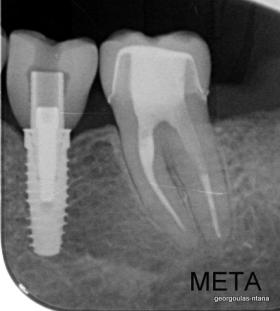

Η ασθενής ήταν δυσαρεστημένη με την αισθητική εμφάνιση των δοντιών της, κυρίως των άνω και κάτω πρόσθιων, τα οποία είχαν εκτεταμένες εμφράξεις σύνθετης ρητίνης που είχαν αποχρωματιστεί. Κάποια από τα οπίσθια δόντια έφεραν κακότεχνες προσθετικές αποκαταστάσεις (γέφυρα, στεφάνες) ενώ κάποια άλλα ήταν τερηδονισμένα. Η ασθενής επιθυμούσε το καλύτερο δυνατό αισθητικό αποτέλεσμα. Για το λόγο αυτό αποφασίστηκε να τοποθετηθούν μεμονωμένες ολοκεραμικές στεφάνες από διπυριτικό λίθιο (Emax) σε όλα τα δόντια της άνω και κάτω γνάθου, ώστε να εξασφαλιστεί το καλύτερο αισθητικό αποτέλεσμα. Χρησιμοποιήθηκε η τεχνική MIPP (Minimally Invasive Prosthetic Procedures) με ελάχιστη αποκοπή οδοντικών ιστών και μονολιθικές αποκαταστάσεις Emax στα οπίσθια δόντια.  Στη θέση του κάτω αριστερού πρώτου γομφίου, ο οποίος έλειπε και είχε αντικατασταθεί με γέφυρα που στηρίζονταν στα διπλανά δόντια, αποφασίστηκε να τοποθετηθεί εμφύτευμα. Σε όλη τη διάρκεια της θεραπείας η ασθενής ήταν καλυμμένη με προσωρινές προσθετικές αποκαταστάσεις.